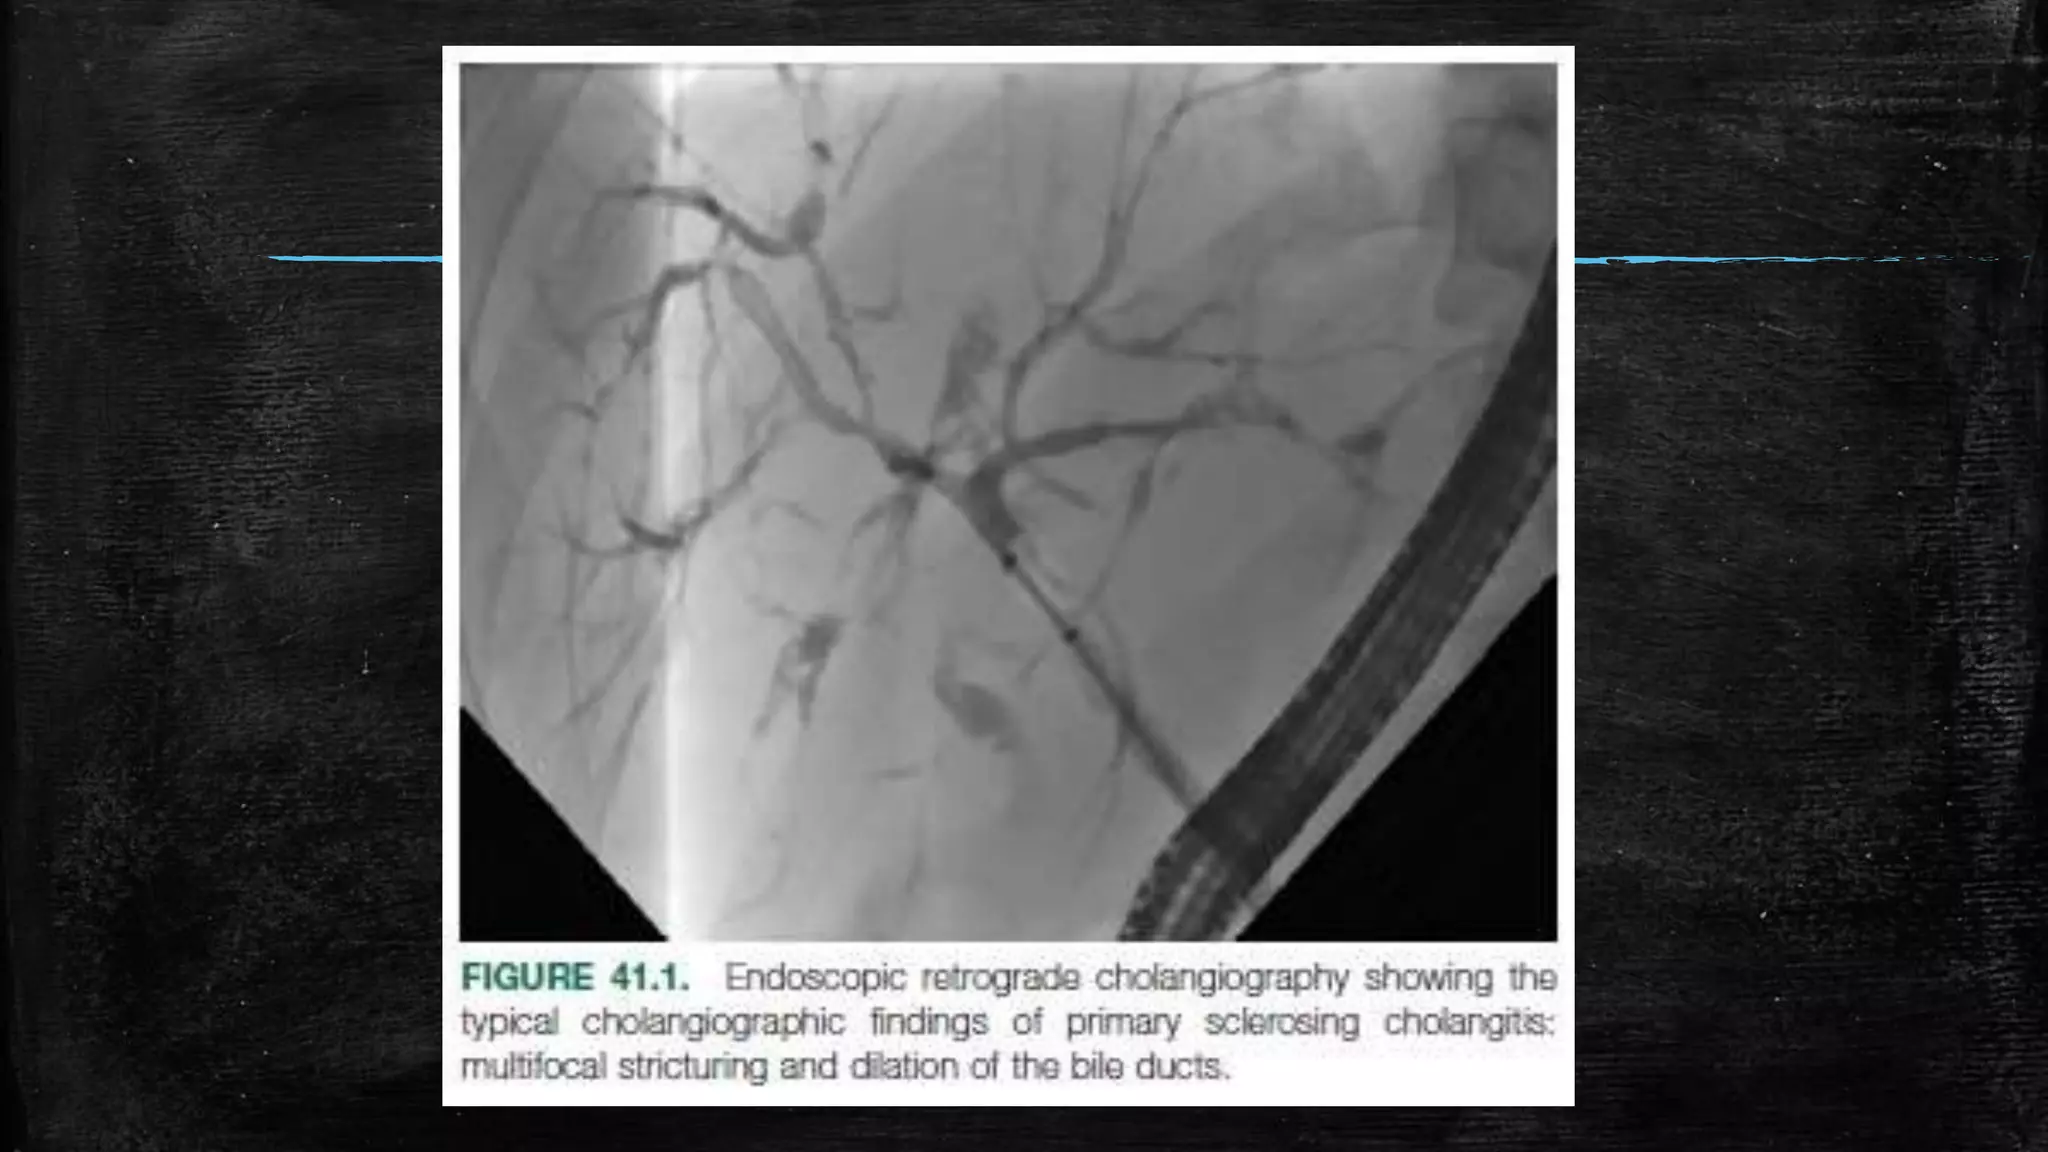

▪ (2) cholangiography demonstrating multifocal intrahepatic and/or

extrahepatic biliary strictures and segmental dilations

Diagnosis ▪ Clinical featureswith ▪ (1) a chronically cholestatic serum biochemical profile ▪ (2) cholangiography demonstrating multifocal intrahepatic and/or extrahepatic biliary strictures and segmental dilations ▪ (3) compatible features (e.g., chronic cholangitis, ductular proliferation, and periductal fibrosis) on liver biopsy